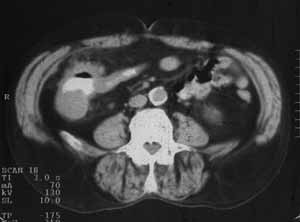

Рис. 2. Рак слепой кишки: неравномерное утолщение стенок, инфильтрация окружающей клетчатки.